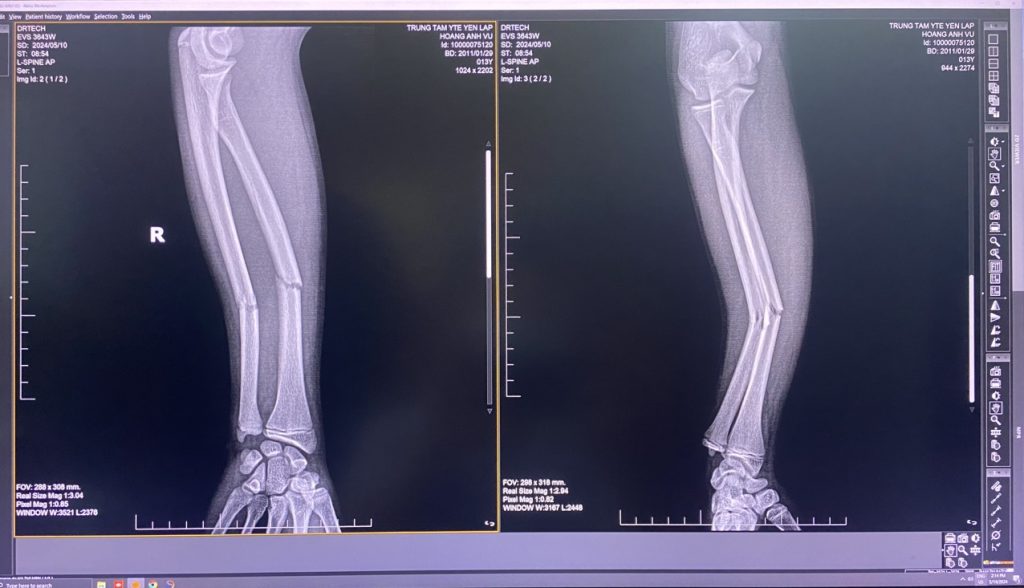

Những buổi học cuối năm, sau khi đã hoàn thành các bài kiểm tra học kỳ, cậu học sinh lớp 7, Hoàng Anh V. không may bị ngã. Khi ngã V. chống tay phải xuống nền cứng, sau ngã V. thấy cẳng tay phải đau nhức, di lệch, vận động hạn chế. Sau 30’ ngã, […]